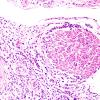

PERIPHERAL NEUROPATHY

15 NEUROPATHY ASSOCIATED WITH NEOPLASIA

1 Neoplastic Infiltration (7)